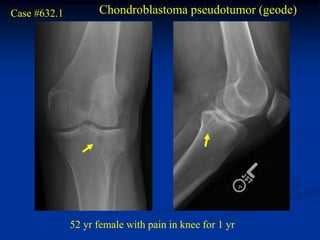

Case #632.1         Chondroblastoma pseudotumor (geode)

52 yr female with pain in knee for 1 yr

Cor T-1   T-2

Axial T-2

Sag T-1